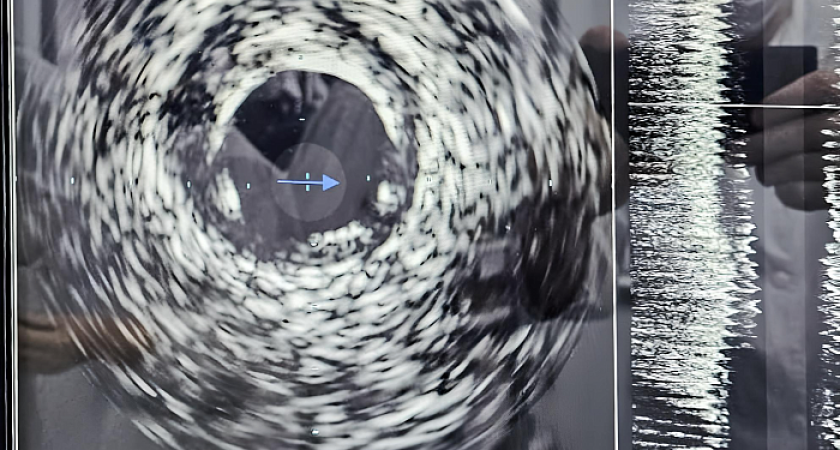

О новой уникальной технологии внутрисосудистого ультразвукового исследования, которую теперь используют в Кировской областной клинической больнице  сообщили в  облправительстве. Инновация помогает выявить проблему на ранней стадии и обойтись без операций на сердце.

Проводимое с помощью ультразвукового датчика исследование поможет узнать о составе атеросклеротической бляшки, степени сужения артерии и многом другом, рассказал заведующий отделением Евгений Перевалов. Метод позволит предотвратить развитие серьезных заболеваний, но самым главным достоинством инновации является возможность продлевать жизни пациентам, помогая избежать открытого хирургического вмешательства.